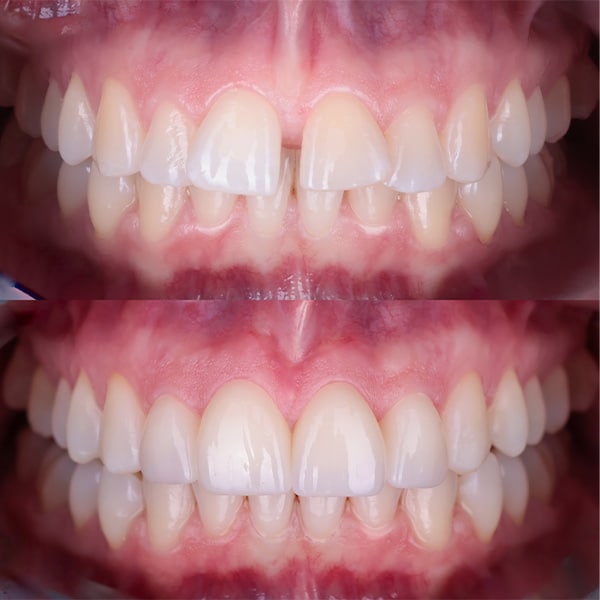

Gingiwoplastyka to procedura chirurgiczna, która polega na modelowaniu i konturowaniu dziąseł w celu poprawy estetyki uśmiechu. Zabieg ten jest bezkrwawy, bezpieczny i bezbolesny, a jego efekty są natychmiastowe i trwał

- Modelowanie Dziąseł

- Chirurg precyzyjnie usuwa nadmiar tkanki dziąsłowej za pomocą specjalistycznych narzędzi lub lasera, modelując linię dziąseł tak, aby wizualnie wyeksponować więcej zęba.

- Cały proces jest kontrolowany i monitorowany, aby uzyskać symetryczny i naturalny wygląd dziąseł.

Zalety Gingiwoplastyki

- Poprawa Estetyki Uśmiechu: Korekta linii dziąseł znacząco poprawia estetykę uśmiechu, czyniąc go bardziej harmonijnym i atrakcyjnym.

Gingiwoplastyka to efektywny sposób na poprawę estetyki uśmiechu i zwiększenie pewności siebie. W naszej klinice dbamy o to, aby każdy zabieg był przeprowadzony z najwyższą precyzją i dbałością o komfort pacjenta. Dzięki nowoczesnym technologiom i doświadczeniu naszych specjalistów, możemy zapewnić pacjentom piękny i zdrowy uśmiech.